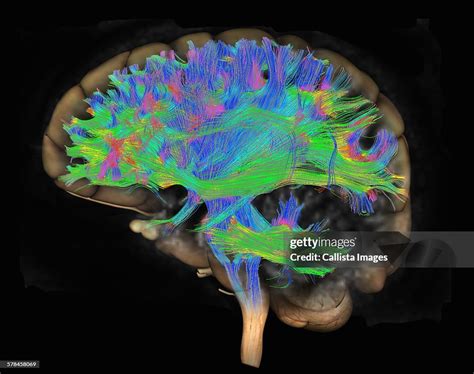

what is dti mri

what is dti mri. There are any references about what is dti mri in here. you can look below.